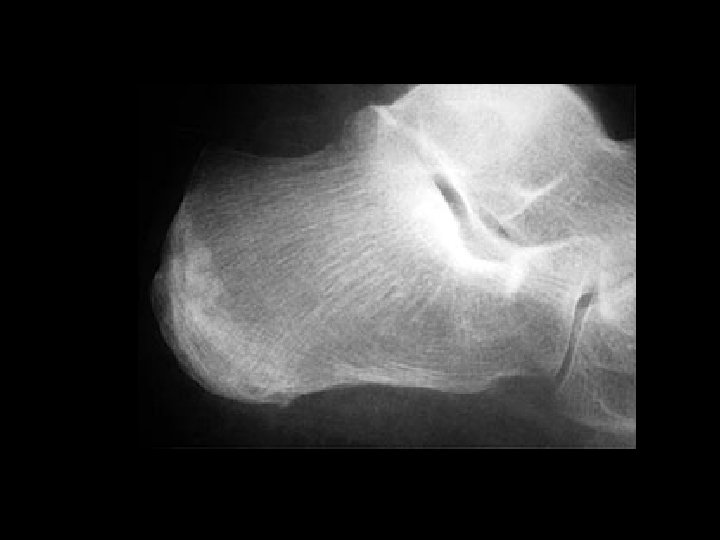

Calcaneal stress fracture • Findings: – Patchy linear and arclike sclerosis in the posterior calcaneous • ddx: – NONE! – This is an Aunt Minnie!